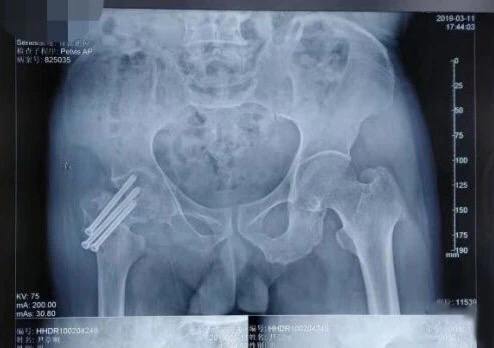

(术前X光片)